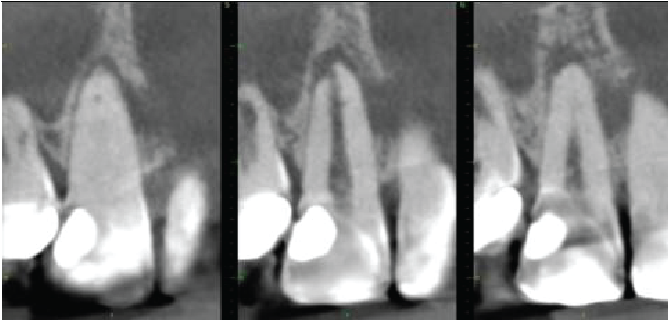

Cross sectional images of UR2

Mesio-distal

Labio-palatal

Axial

The UR2 is incompletely erupted, with its cervical margin more superiorly placed than on adjacent teeth, with the periodontal bone level correspondingly placed. The tooth is crowned. Dens invaginatus anomaly also seen (Oehler type I), matching that on the contralateral tooth. There is extensive external cervical root resorption arising distally, with a large surface defect and with root canal involvement. The difficulty in seeing the periodontal ligament around the apical half of the root probably indicates some areas of ankylosis. No periapical inflammatory pathosis.